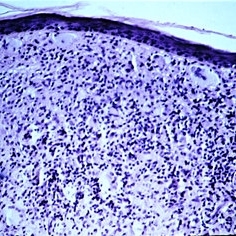

Slide 5-2 Slide 5-2Feb 20 2019 by Lancaster Course in Ophthalmology The thickened epidermis shows acanthosis (prickle cell proliferation) and parakeratosis (retention of nuclei in desquamating surface-layer cells). Condition/keywords: acanthosis, epidermis, Keratosis pilaris (KP), prickle cell proliferation